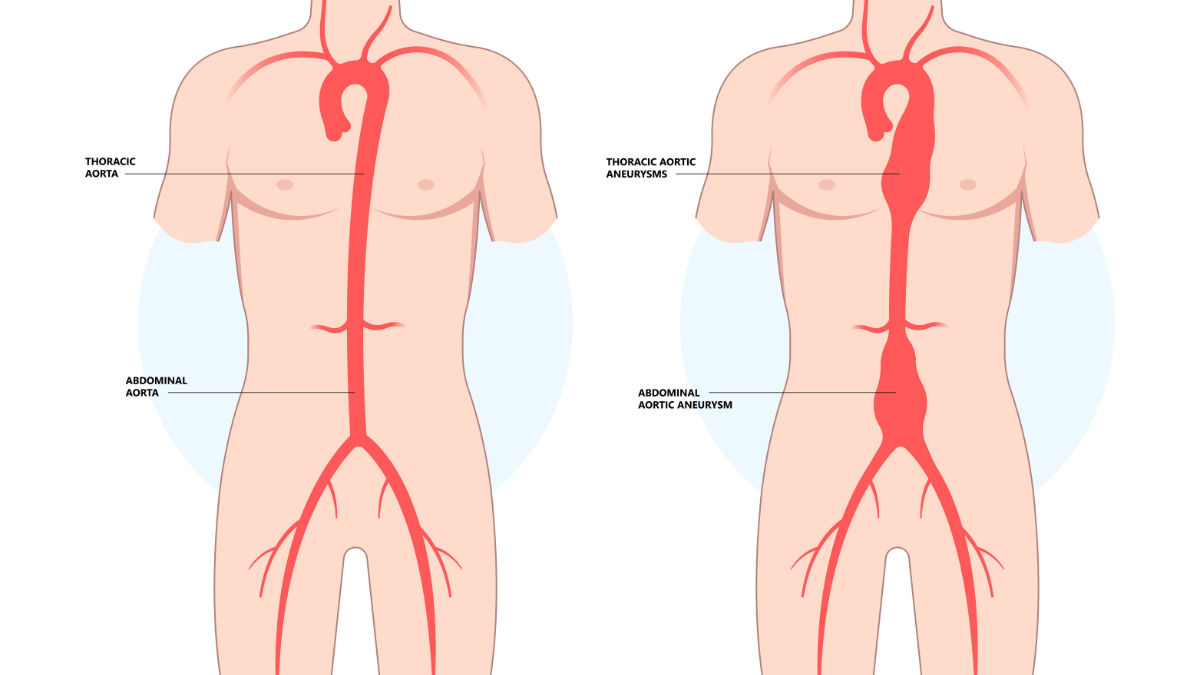

Abdominal Aortic Aneurysm (AAA): What You Need to Know

Discover expert care for Abdominal Aortic Aneurysm (AAA) at Northern Heart Hospital. Learn about cau…